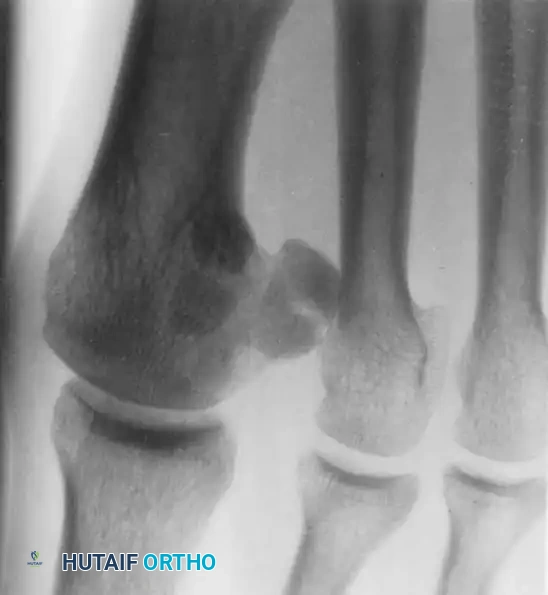

Fig. 78-99 A and B, Plantar flexed first ray with callus beneath the tibial sesamoid. C, On a Harris pressure mat, note the increased pressure beneath the tibial sesamoid. D, The tibial sesamoid has been removed, and the articular surface and corresponding facet of the metatarsal head show degenerative changes.